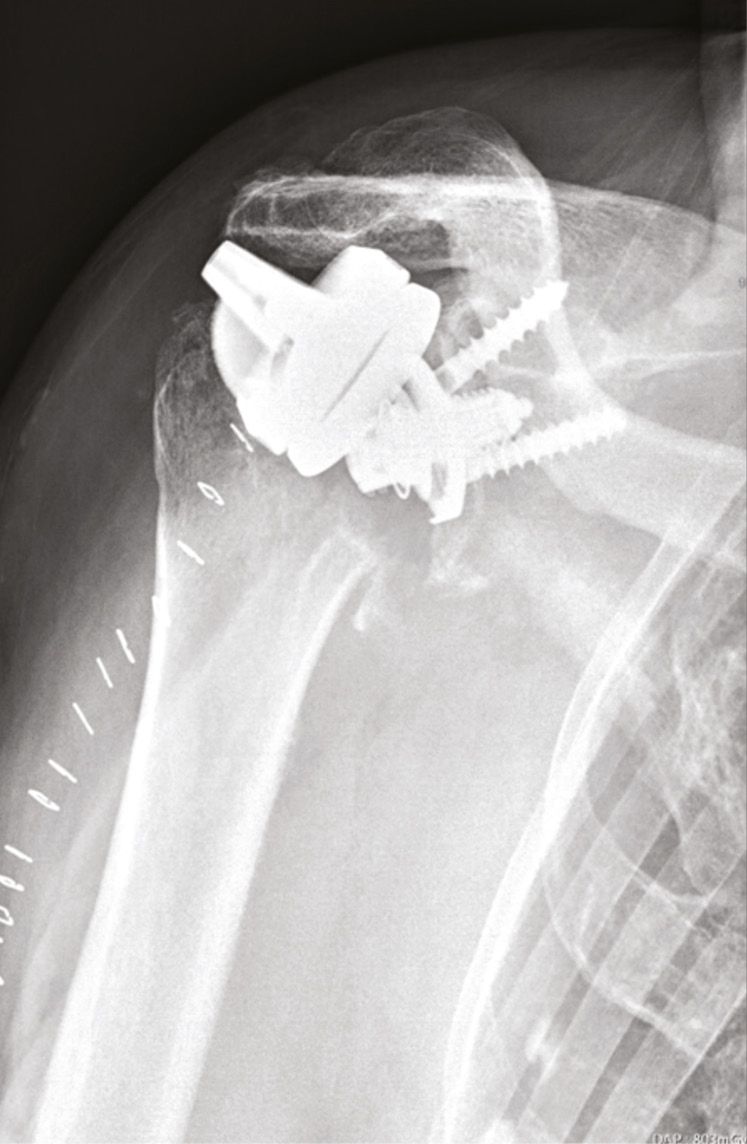

- 4 humeral loosenings (Fig. 3).

The four cases of non-traumatic early loosening were due to poor assessment of bone density and the use of a metaphyseal reamer that aggravated the loss of bone stock. Having continued to use this technique, we have so far performed over 250 stemless RTSA (May 2014–Dec 2021) with one single other recent case of loosening following a fall in the first two weeks. We would like to describe the technique for a stemless RTSA in more detail.